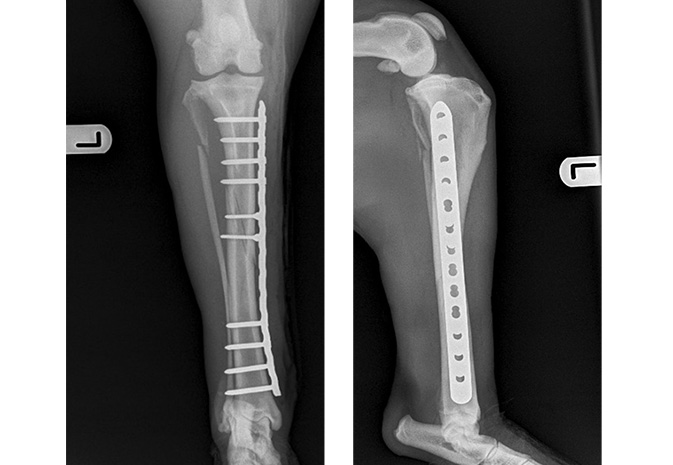

Internal fixation was recommended to address this injury. Within 24 hours of presentation, Denzyl underwent surgery wherein the tibia was reconstructed with screws and a plate.

Fracture repaired with Locking Compression Plate